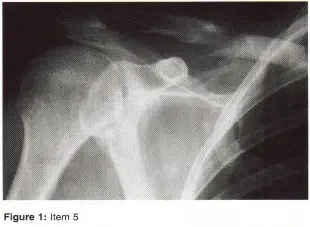

• الأشعة السينية (X-rays): هي الخطوة الأولى في معظم حالات إصابات العظام والمفاصل. تُظهر صورًا للعظام وتُساعد في تشخيص الكسور (مثل كسور عظم الفخذ أو الترقوة)، والخلوع، وتشوهات العظام (مثل الجنف أو تشوهات النمو)، وتغيرات التهاب المفاصل (تآكل الغضروف، النتوءات العظمية). كما تُستخدم لتقييم التئام الكسور بعد العلاج.

• صورة شعاعية لكسر في رأس عظم العضد

• التصوير بالرنين المغناطيسي (MRI): يُعد التصوير بالرنين المغناطيسي الأداة الأكثر دقة لتقييم الأنسجة الرخوة مثل الأربطة والأوتار والغضاريف والعضلات والأعصاب. يُستخدم لتشخيص تمزقات الرباط الصليبي، وتمزقات الغض